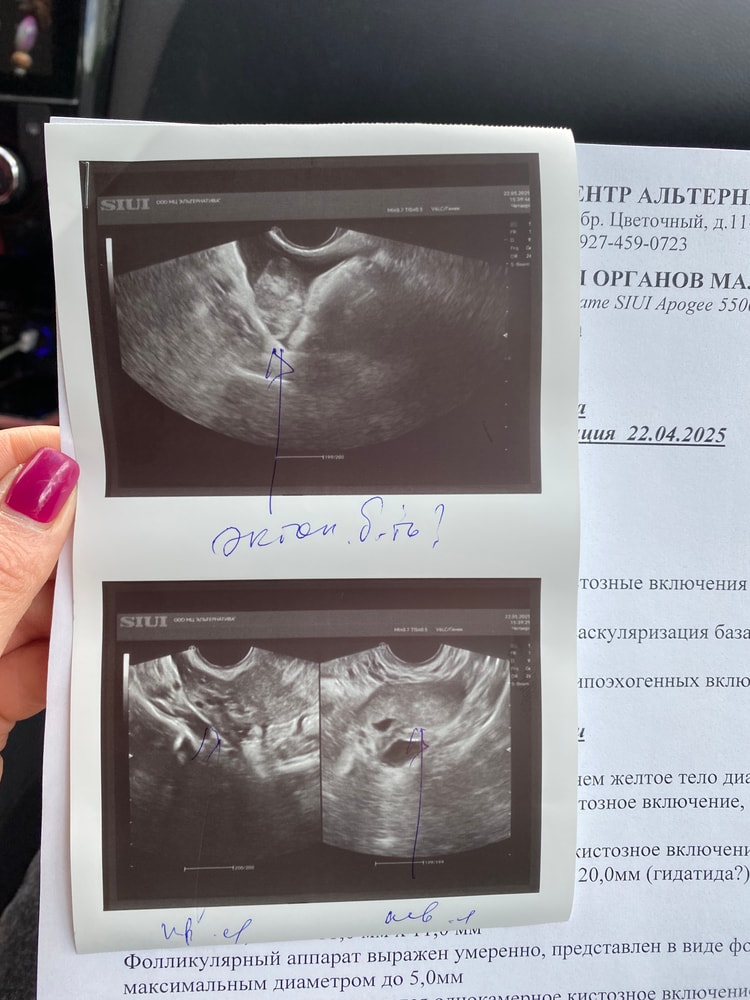

Хгч на той неделе был 1013, до позавчера хгч упал до 356. Сегодня сдала еще раз, жду. вчера сходила на 2 узи, одна написала внематочная справа 5 недель,но говорит раз хгч падает возможно замершая в трубе. 2 узист написала «нельзя исключить трубную беременность» и тоже говорит хгч же падало я в замешательстве! Сегодня жду результат хгч и буду решать ехать в больницу или нет. еще вчера пришли как будто месычные как обычно, но с задержкой в 3 дня. Сейчас разгоняются. Узи прикреплю. Сейчас если лягу выходные, я и так мониторю хгч сама и на узи хожу. Вроде говорят в таких случаях какой то укол делают на выкидыш, но у меня пока месячные пришли.